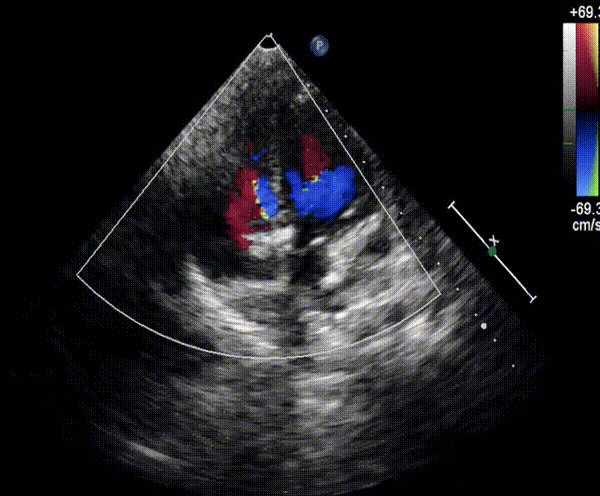

术后造影及经胸超声结果显示MemoSorb®全降解封堵器形态良好,封堵完全,无残余分流,主动脉无返流,遂完全释放封堵器,回收成型线,封堵效果理想,顺利完成手术。

▲封堵器到位后瓣上造影无返流

▲术后造影